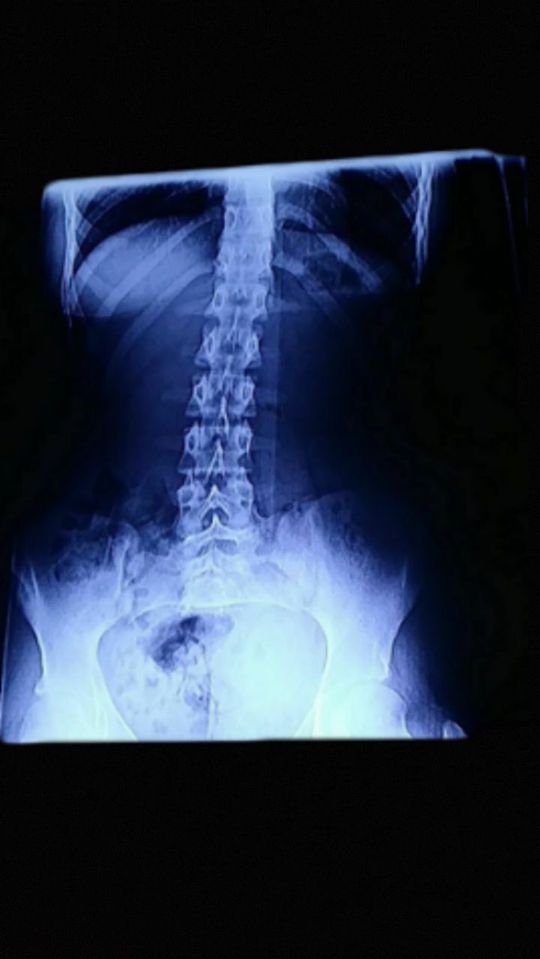

X-ray of chest and abdomen

Not a doctor but the thing I instantly notice is the crooked spine